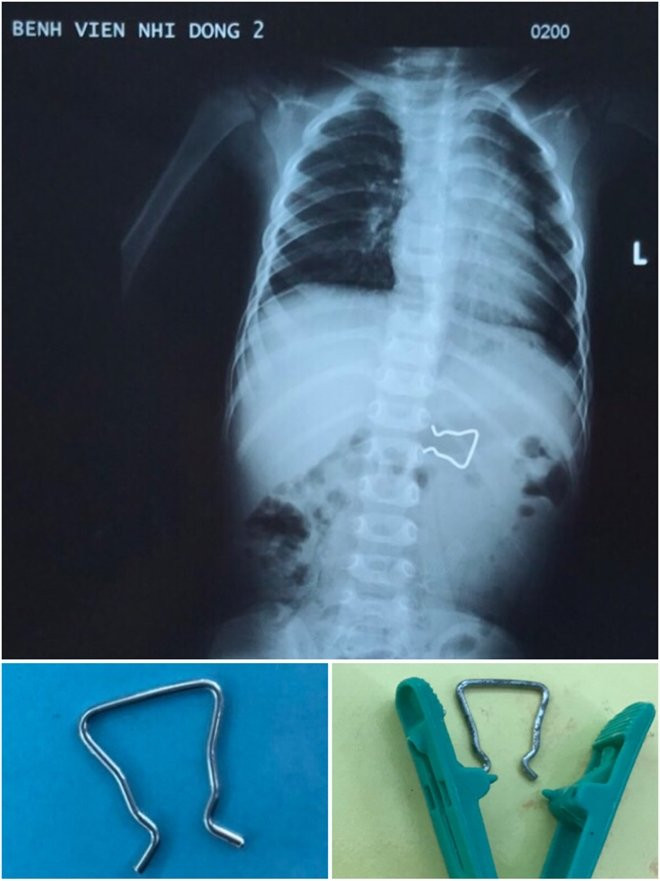

Tại bệnh viện Đắk Lắk, kết quả chụp X-quang bụng ghi nhận có hình ảnh lờ mờ của dị vật giống như thanh chốt bằng kim loại thường dùng để cố định trong kẹp quần áo. Có thể dị vật trên đã rớt ra và bé nhặt chơi rồi nuốt phải.

Sau khi thăm khám, Bệnh viện Đắk Lắk chuyển bé K. lên Bệnh viện Nhi Đồng 2 (TP. HCM). Khi vừa tiếp nhận bệnh nhân, ekip nội soi tiêu hóa nhận định đây là 1 trường hợp khó vì hình dáng dị vật có 2 cạnh sắc nhọn kích thước lớn, khi gắp dị vật có thể gây tổn thương nhiều hơn niêm mạc đường tiêu hóa.

Dị vật là đoạn dây inox cong, gấp khúc, khớp với phần còn lại của chiếc kẹp quần áo .

Theo BS Nguyễn Minh Ngọc Trưởng khoa Tiêu hóa, Bệnh viện Nhi đồng 2 cho rằng, bệnh nhi cần phải được tiến hành gắp dị vật ngay trước khi nó di chuyển sâu hơn, gây biến chứng thủng ruột. Các y bác sĩ đã nhanh chóng liên lạc và cùng phối hợp với chuyên gia nội soi của Bệnh viện Chợ Rẫy và gặp dị vật ra ngoài an toàn.